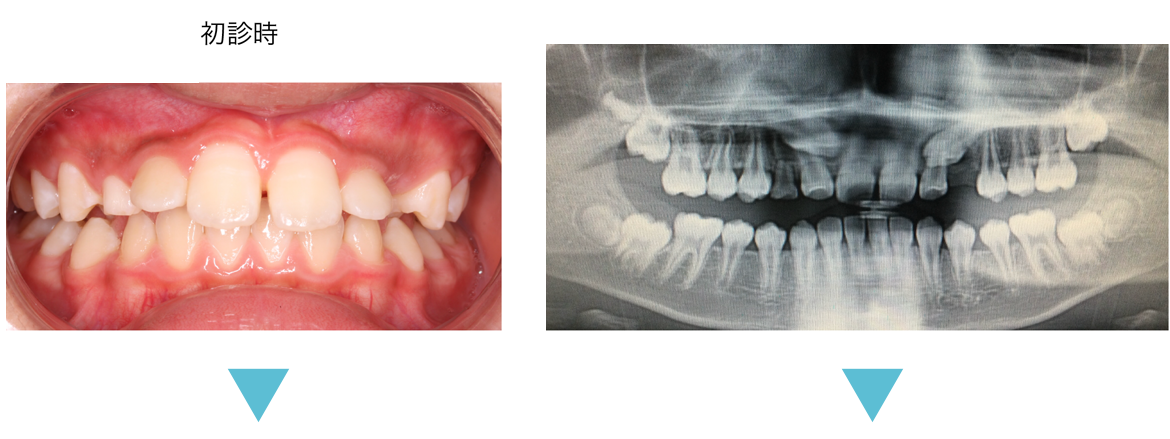

歯並びが混み合っている原因は歯の大きさに対して歯列(顎の大きさ)が小さいことが多いです。

硬いものをよく噛んでいれば顎が成長するのでしょうが、柔らかいものを食べている私たちは顎が小さくなっています。そこで歯列を大きくする拡大装置を使って歯列全体を大きくして永久歯が綺麗に並ぶように治療します。